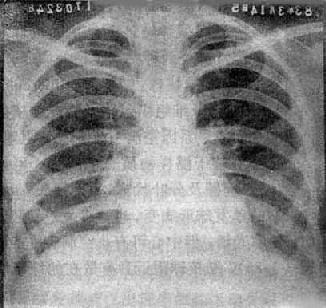

慢性血行播散型肺结核

图3-1-23 慢性血行播散型肺结核

两肺野布满大小不一、密度不同、分布不均的病灶,

下野较少,膈位置低而平